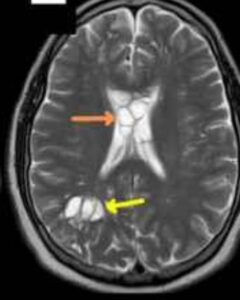

Investigațiile imagistice i-au schimbat viața: medicii au identificat în creier leziuni compatibile cu ouă de tenie, diagnosticul fiind cisticercoză — o infecție cauzată de larvele acestui parazit care pot ajunge și în țesutul nervos.

Investigațiile au confirmat prezența cisticercozei

Potrivit medicilor, suspiciunea a apărut după ce durerea de cap s-a intensificat iar tratamentele uzuale nu și-au mai făcut efectul. O serie de tomografii cerebrale a relevat imagini sugestive pentru prezența unor formațiuni parazitare, ceea ce a condus la stabilirea diagnosticului de cisticercoză. Afecțiunea este rară, dar bine documentată: larvele de tenie pot migra și se pot fixa în diverse țesuturi ale corpului, inclusiv în creier.